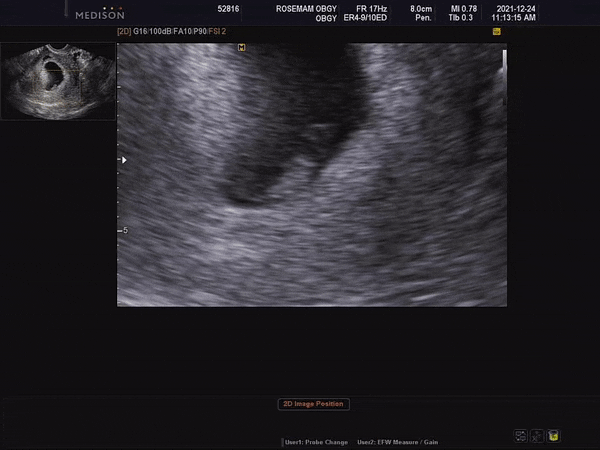

[임신 6주] 두개의 심장이 되었다

21년 12월 24일 크리스마스이브날 6주 검진이 있어 로즈맘산부인과에 방문했다 접수를 하고 혈압과 몸무게...